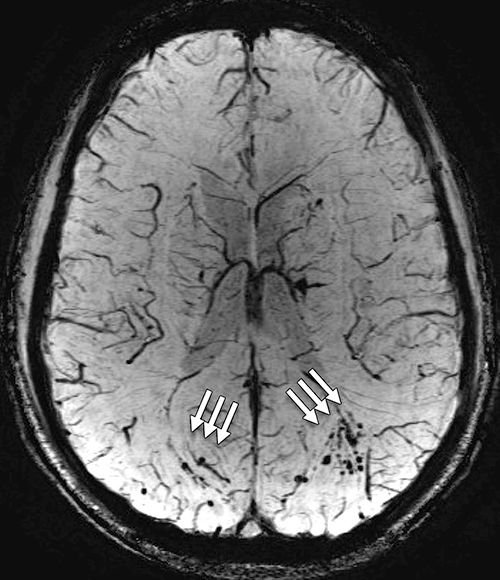

An earlier scan of a patient’s brain with traumatic brain injury is better for greater detection of microhemorrhages.